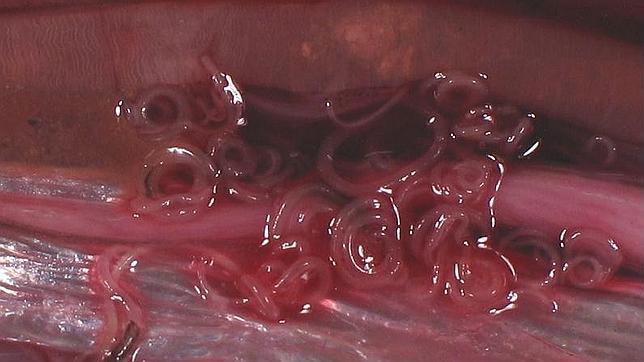

Es un gusano nematodo que pasa su ciclo vital en el tubo digestivo de peces y mamíferos marinos, donde vive a costa de ellos. Cuando el ser humano ingiere pescado infectado, este gusano puede causarle alteraciones digestivas y reacciones alérgicas.